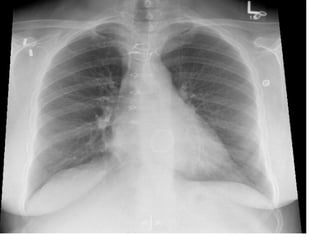

The document discusses several different cardiac conditions and test results including atrial fibrillation with complete heart block, second degree 2:1 heart block, complete heart block, atrial flutter with 2:1 block, amyloidosis indicated by an echocardiogram showing severe LVH, speckled appearance and low voltage limb leads on ECG, inferolateral reversible ischemia of moderate degree found on a graft study for a post-CABG patient which also showed an occluded superior OM and diseased OM2 and OM3 that were stented.